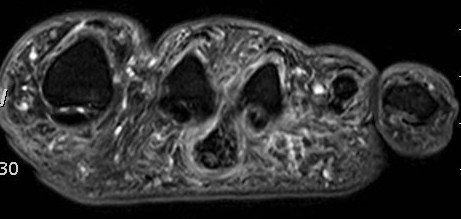

MRI

Focal oval shaped lesions within the plantar fascia